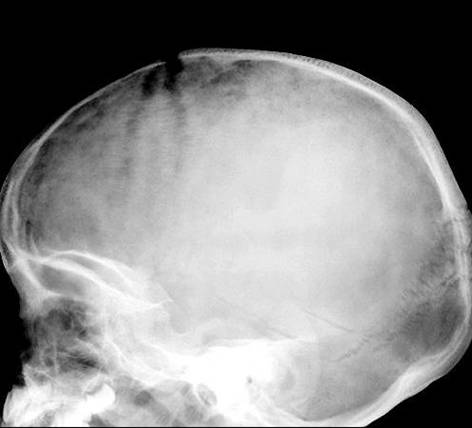

Lytic Lesions in Children

l

Eosinophilic

granuloma

Neuroblastoma

Leukemia